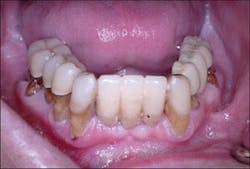

An interim immediate complete mandibular denture was fabricated prior to extraction of the mandibular teeth (Figure 2). The mandibular teeth were extracted and necessary alveoloplasty was performed (Figure 3).

Figure 2 - Interim denture ready to be converted to fixed provisional restoration